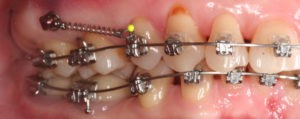

Искривление окклюзионной кривой (плоскости смыкания зубов), возникшее в результате парадонтита, успешно удалось устранить, используя накусочные брекеты на верхних резцах и микроимплант, установленный во фронтальном участке нижней челюсти: